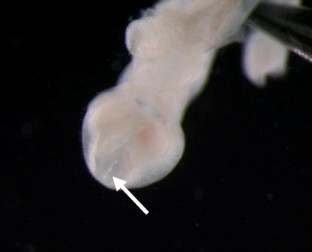

Teratogenic effects caused by a new nitroimidazopyridazine were examined in Wistar (WU) rats after repeated oral administration of 0, 2.5, 10, and 40 mg/kg, given on days 6–17 post coitum (p.c.) (Day of mating = Day 0) in a regular study on embryo-fetal development according to ICH S5A. At day 20 p.c., fetuses were removed and carefully examined under a dissecting microscope for external, visceral and skeletal malformations. The exposure to the high dose of the test compound during the organogenesis and early histogenesis periods of prenatal development induced prominent CNS malformations (exencephaly, neural tube defects (NTD)) associated with external malformations (hyperflexion of the forelimbs). To support the data from this study additional histological evaluation of the brains was performed with the following results: disorganization of the cerebral cortex associated with ectopic subcommissural organs. Additionally, an in vitro test (whole embryo culture, WEC) showed alterations of the developing neural tube after the incubation of rat embryos with the test compound on gestation days 9.5–11.5. Our data demonstrated that nitroimidazopyridazine caused NTDs and limb malformations during organogenesis. Based on these data the further development of the test compound was stopped.